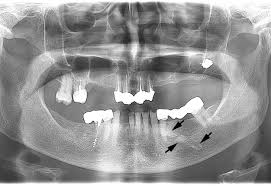

horizontal bone loss

most common in periodontitis

fairly even reduction in the height of the alveolar bone

vertical bone loss (angular bone loss)

less common

uneven reduction in the height of the alveolar bone